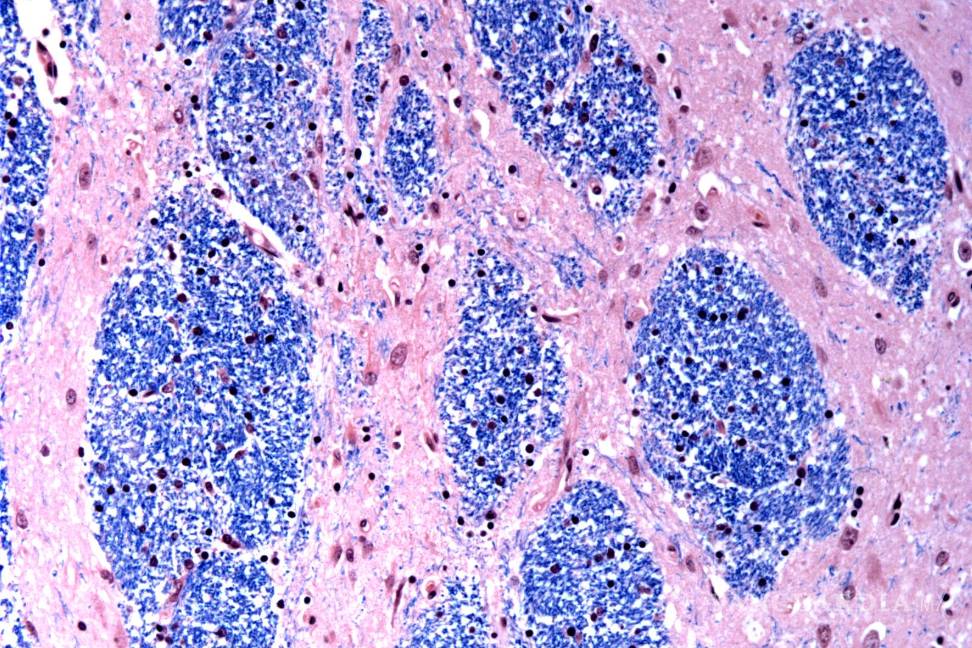

Científicos del Broad Institute de MIT y Harvard, el Hospital McLean en Massachusetts y la Facultad de Medicina de Harvard estudiaron tejido cerebral donado por 53 personas con Huntington y 50 sin ella, analizando medio millón de células.

$!Los científicos están desentrañando el misterio de qué es lo que desencadena la enfermedad de Huntington, un trastorno hereditario devastador y mortal.

Se centraron en la mutación de Huntington, que involucra un tramo de ADN en un gen particular donde una secuencia de tres letras, CAG, se repite al menos 40 veces. En personas sin la enfermedad, esta secuencia se repite sólo de 15 a 35 veces. Descubrieron que los tramos de ADN con 40 o más “repeticiones” se expanden con el tiempo hasta que tienen cientos de CAGs. Una vez que los CAGs alcanzan un umbral de aproximadamente 150, ciertos tipos de neuronas enferman y mueren.